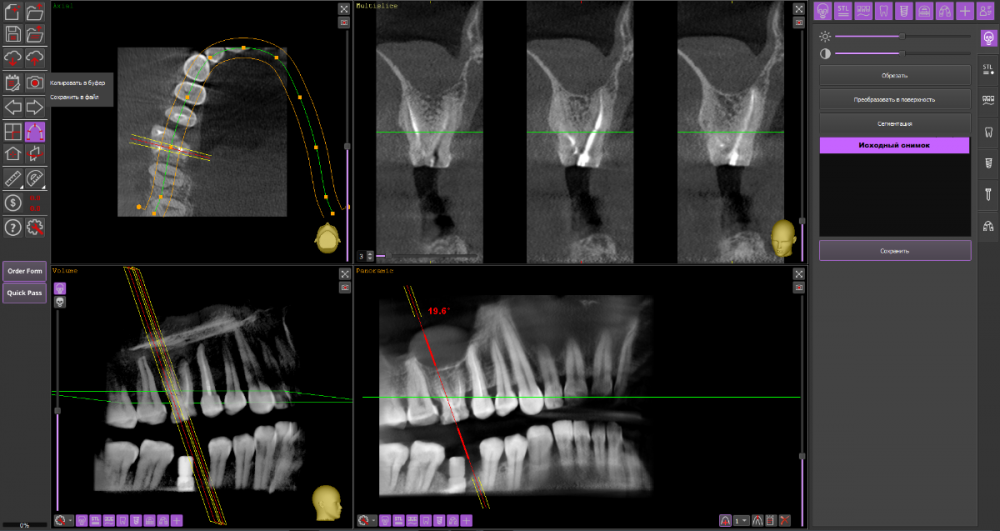

Алексей82 Опубликовано 10 марта, 2022 Автор Поделиться Опубликовано 10 марта, 2022 Здравствуйте. Вот ссылка на КТ. Посмотрите пожалуйста. Или может надо было скрин сделать чегото. https://dropmefiles.com/zxr3f Ссылка на комментарий

wladdX Опубликовано 10 марта, 2022 Поделиться Опубликовано 10 марта, 2022 (изменено) Попробовать поработать в корневых каналах можно, насколько это будет успешно, сказать невозможно. Изменено 10 марта, 2022 пользователем wladdX 1 1 Ссылка на комментарий